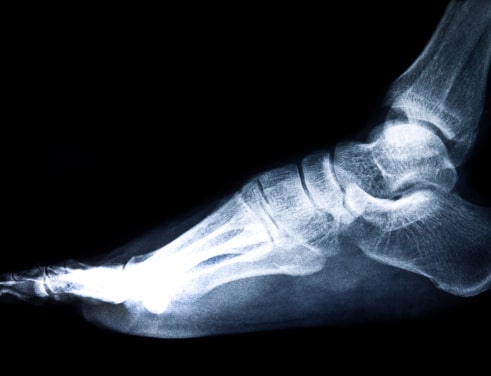

Современная рентгенография стопы остается одним из самых информативных методов исследования опорно-двигательного аппарата. Этот метод позволяет получить детальное изображение костной структуры, выявить патологические изменения и оценить состояние суставов. Медицинский центр «ЗВЕЗДА» в Казани предлагает точную диагностику с использованием передового цифрового оборудования, которое обеспечивает минимальную лучевую нагрузку при максимальной информативности скрининга.

Для получения полноценной картины обычно выполняются два снимка в разных проекциях. При необходимости может быть проведено исследование с нагрузками, что помогает оценить состояние костей под весом тела.